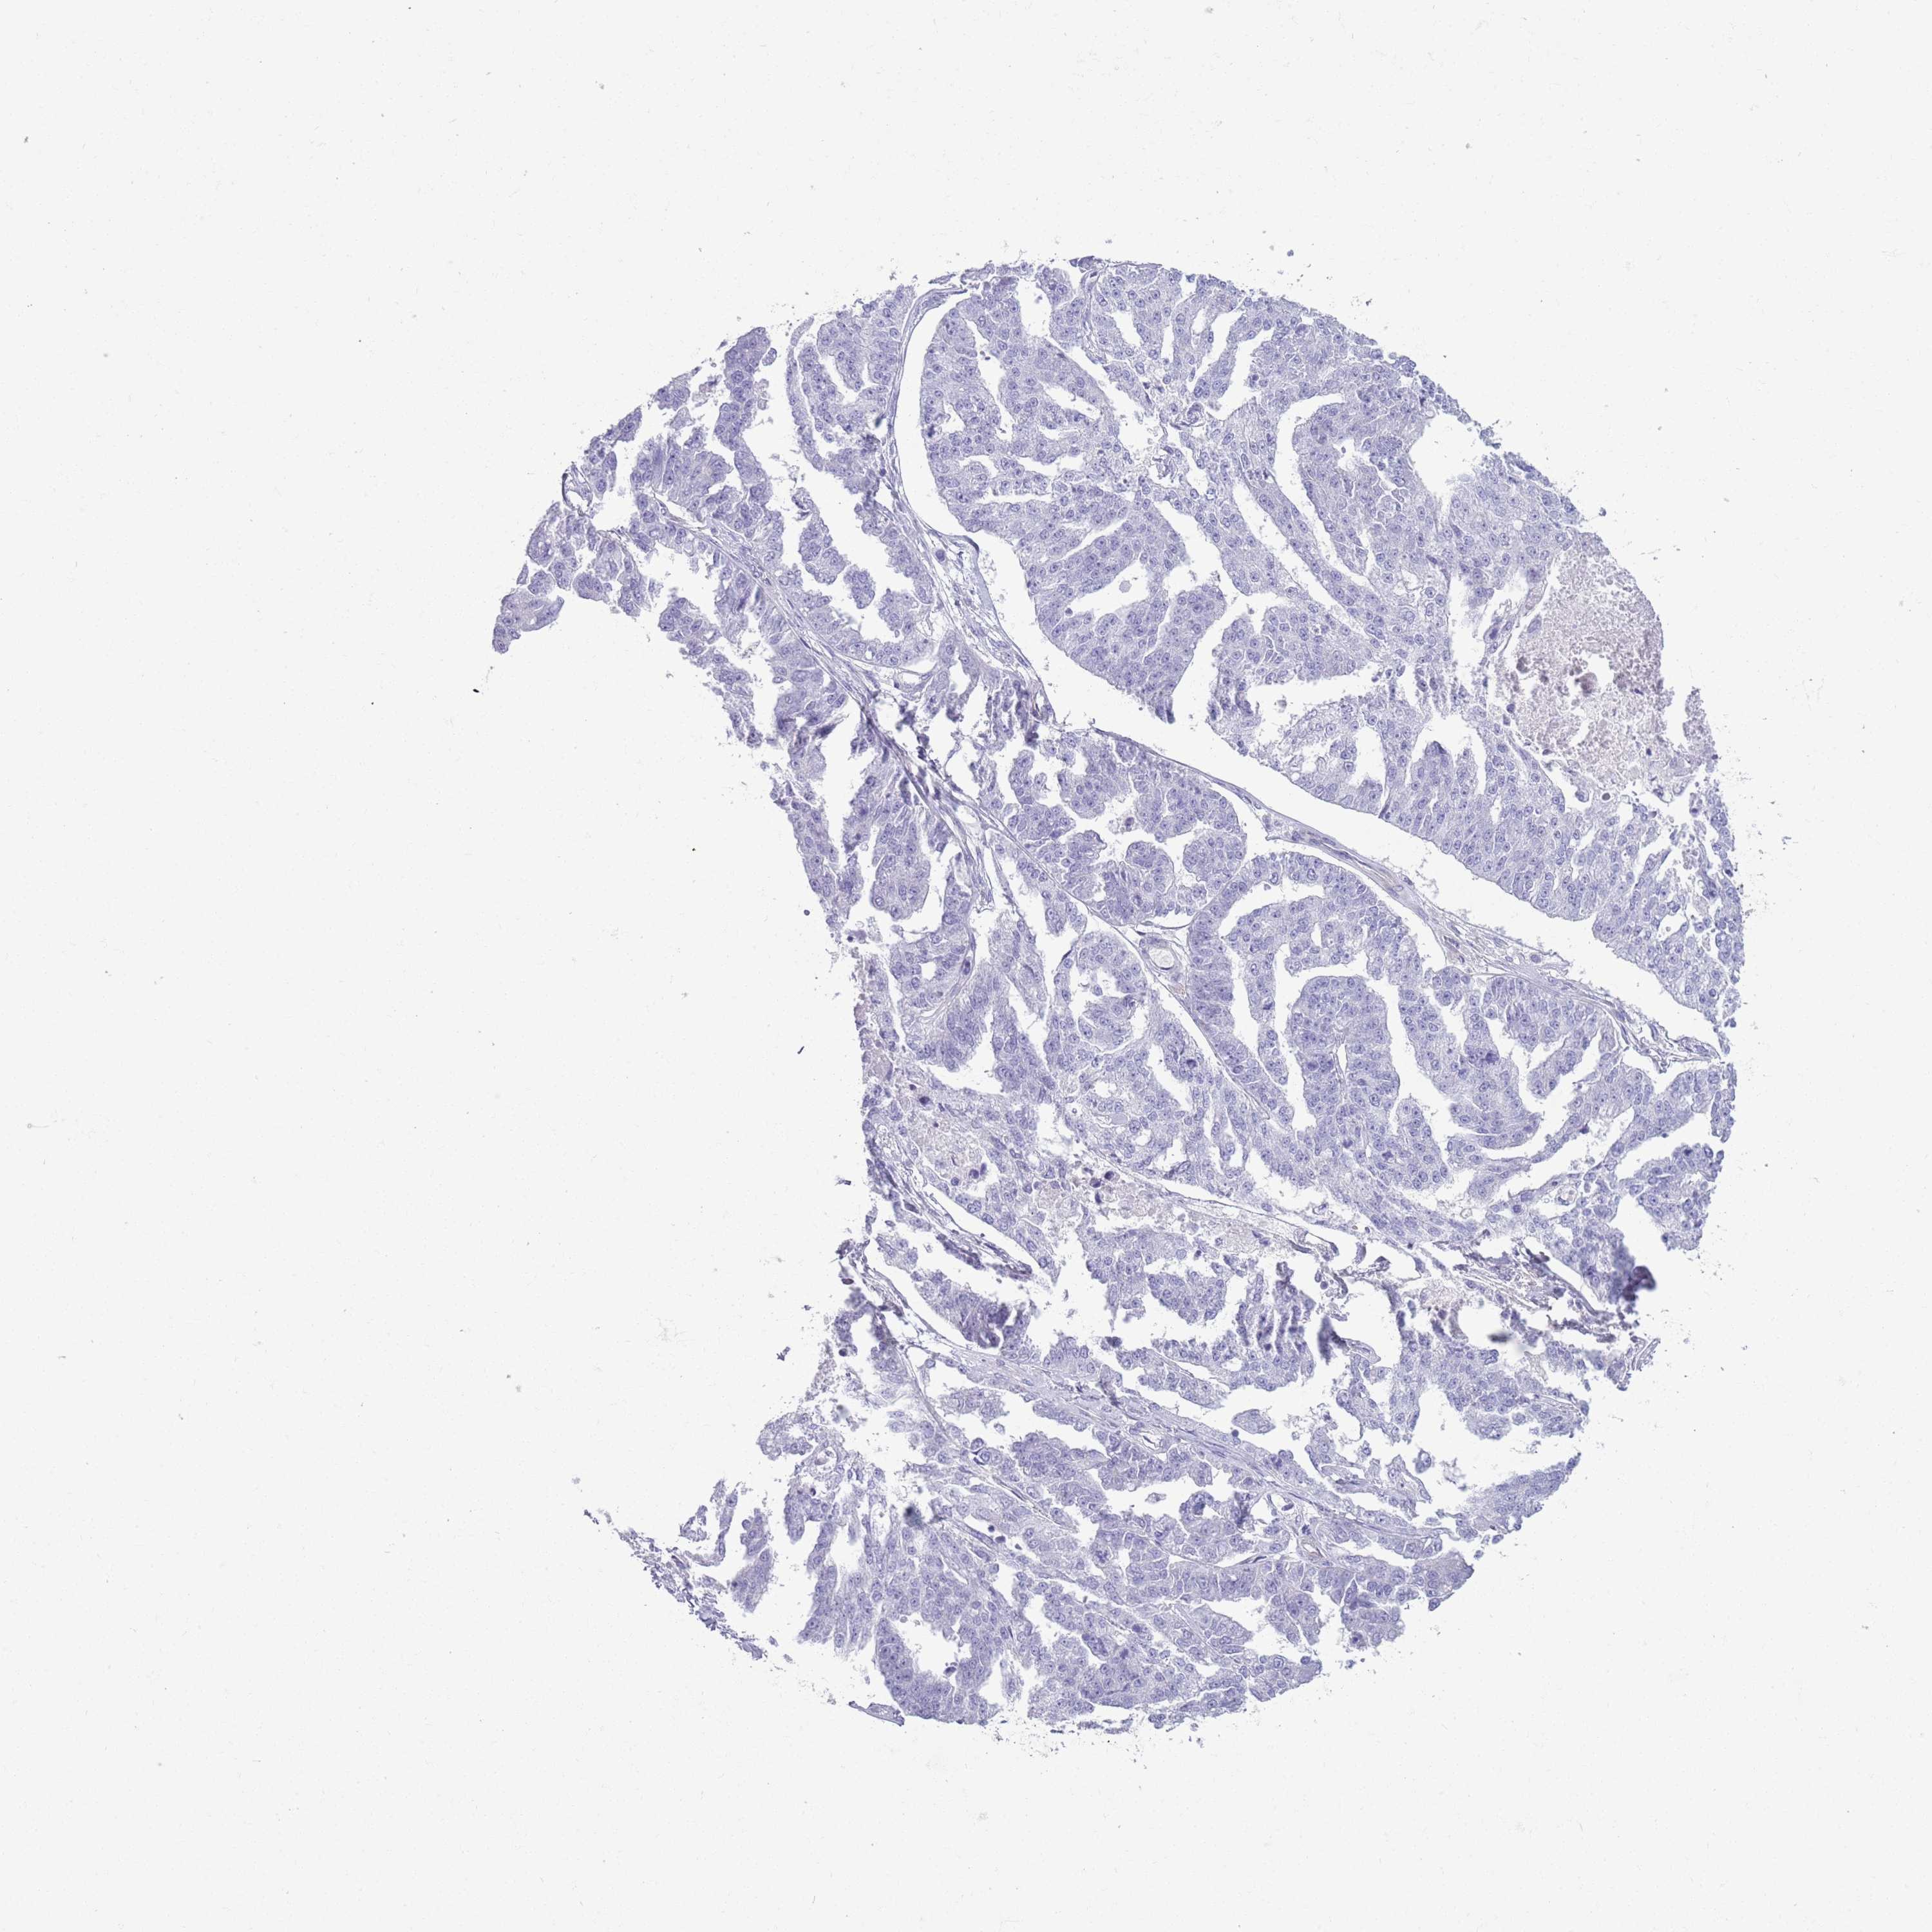

OVARIAN CANCER - Protein expressioni

A mouse-over function shows sample information and annotation data. Click on an image to view it in a full screen mode. Samples can be filtered based on level of antibody staining by selecting one or several of the following categories: high, medium, low and not detected. The assay and annotation is described here.

Note that samples used for immunohistochemistry by the Human Protein Atlas do not correspond to samples in the TCGA dataset.

Antibody stainingi

Antibody staining in the annotated cell types in the current human tissue is reported as not detected, low, medium, or high, based on conventional immunohistochemistry profiling in selected tissues. This score is based on the combination of the staining intensity and fraction of stained cells.

Each image is clickable and will lead to virtual microscopy that enables deeper exploration of all samples and also displays staining intensity scores, fraction scores and subcellular localization as well as patient and tissue information for each sample.

Antibody HPA041301

Antibody HPA044239

Staining

High

Medium

Low

Not detected

Intensity

Strong

Moderate

Weak

Negative

Quantity

>75%

75%-25%

<25%

None

Location

Nuclear

Cytoplasmic/membranous

Cytoplasmic/membranous,nuclear

Cystadenocarcinoma, serous, NOS

Carcinoma, endometroid

Cystadenocarcinoma, mucinous, NOS

Carcinoma, NOS